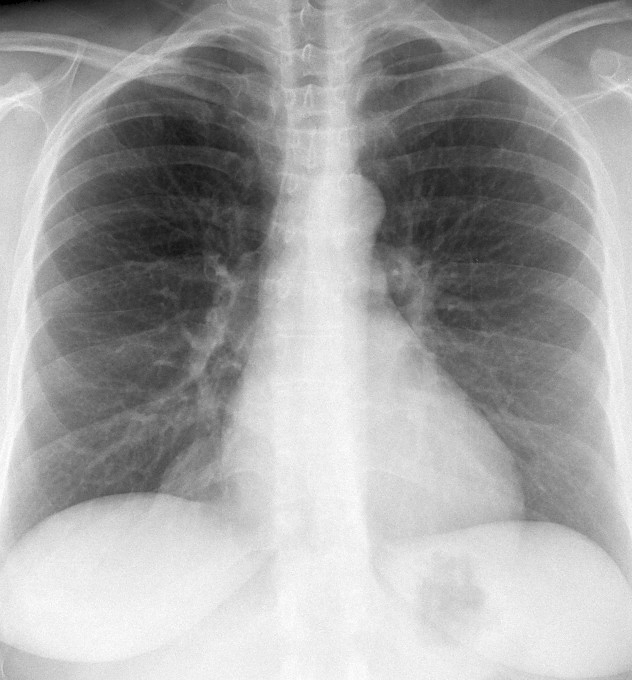

Fat Pad

Case 11a